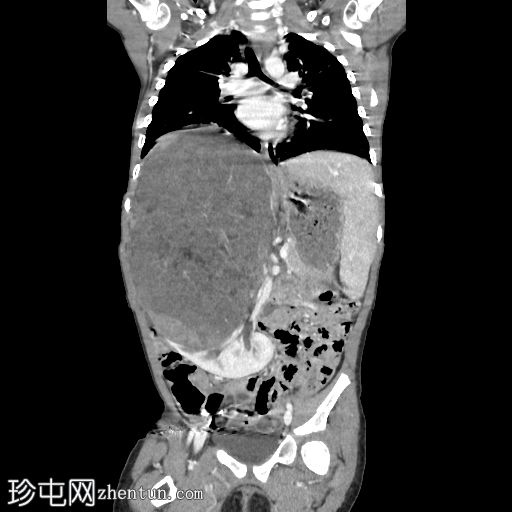

矢状位增强扫描(门静脉期)

冠状位增强扫描(门静脉期)

右肾向下移位至中线,呈水平位。肾上极可见一大小不一、边界相对清晰的肿块。未见明显钙化或坏死。肿块延伸至中线,但未越过主动脉/中线左侧。下腔静脉上段向前左侧移位。尽管移位,右肾静脉和动脉外观正常,未见狭窄/扩张或明显的肾静脉血栓形成。

结肠和小肠袢,尤其是在右侧腹部,向下移位,但外观无明显异常。

未见腹膜后淋巴结肿大。骨骼结构外观正常,无明显的溶骨性或成骨性改变。